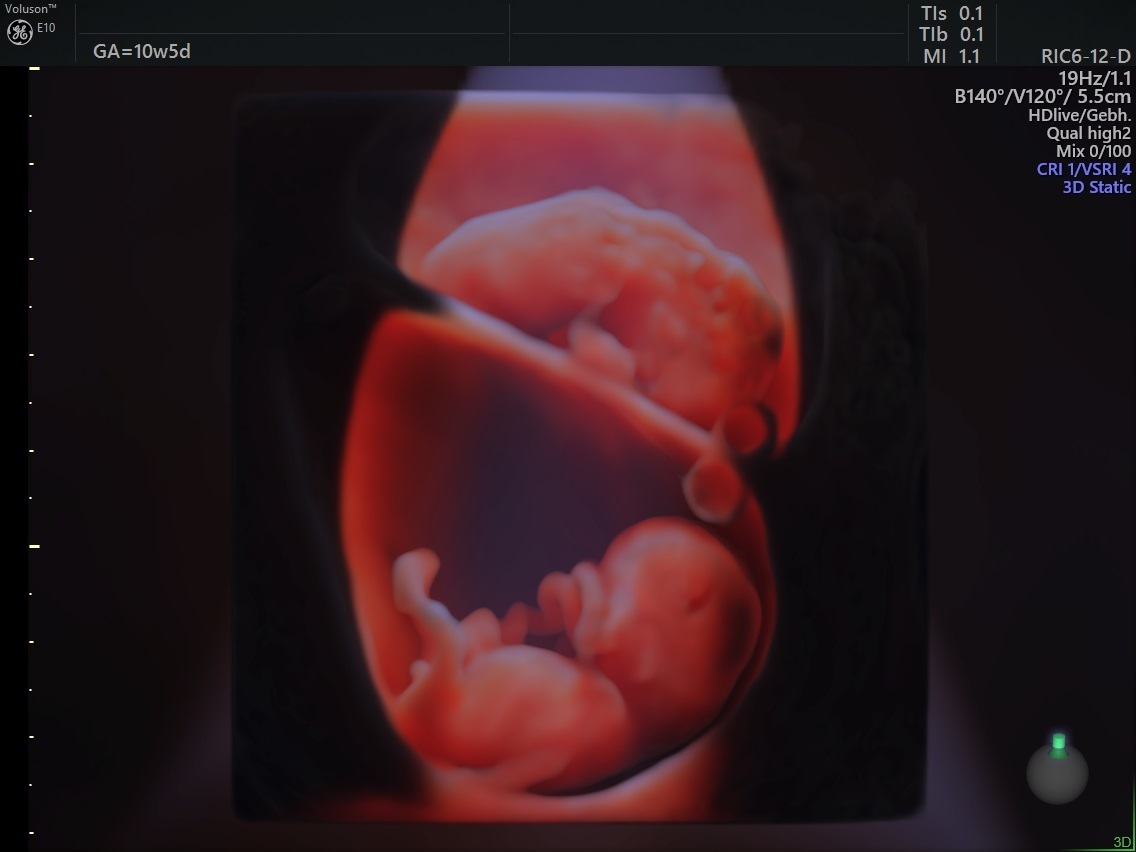

3d Image Of A Baby At 10 Weeks Gestation Baby At 10 Weeks Future Baby Portrait Tattoo